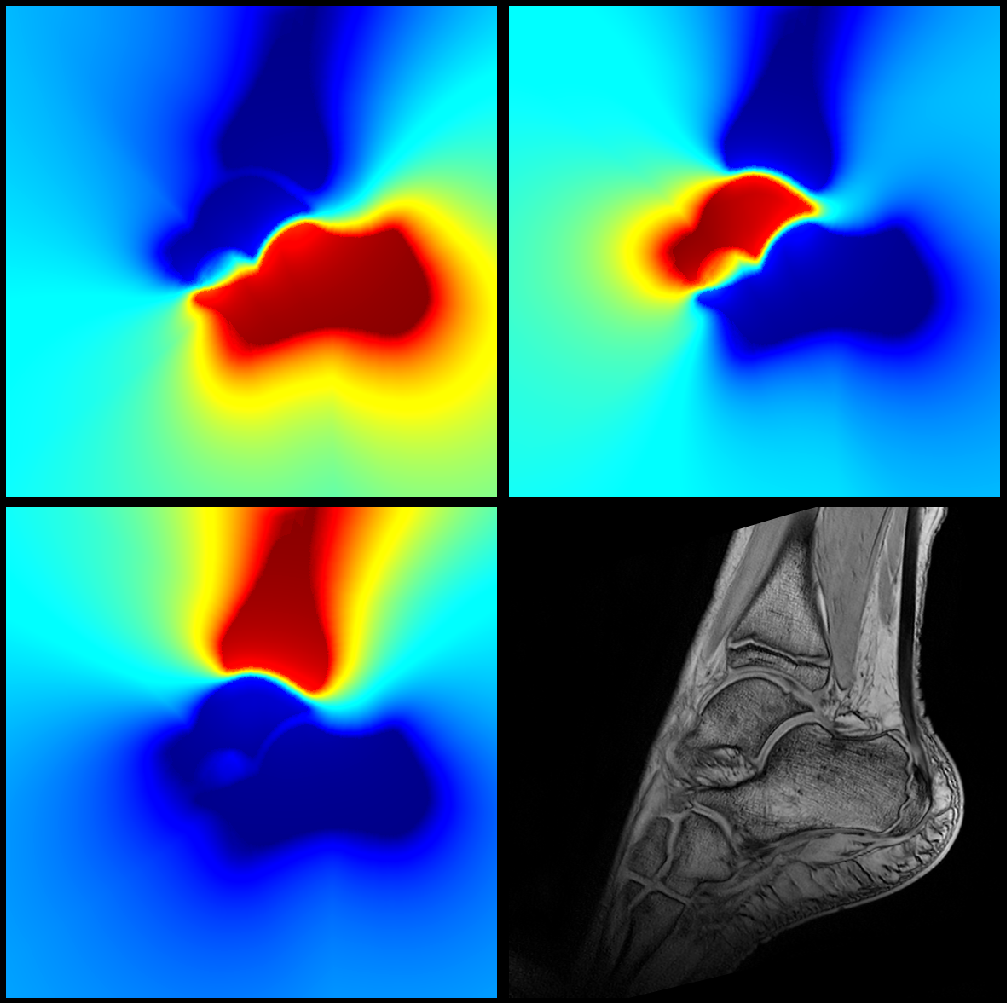

where xDtj𝑥superscript𝐷subscript𝑡𝑗x\in D^{t_{j}}, Bitjsubscriptsuperscript𝐵subscript𝑡𝑗𝑖B^{{t_{j}}}_{i} is the binary mask of the ithsuperscript𝑖𝑡i^{th} component, and dist(.,Bitj)dist(.,B^{{t_{j}}}_{i}) is the corresponding Euclidean distance map at time tjsubscript𝑡𝑗t_{j} (see Figure 3).

Figure 4 illustrates each bone normalized weight function as defined in (32).

Refer to caption

Figure 4: Normalized weighting functions: from up to down, from left to right: for the calcaneus; for the talus; for the tibia; and the associated MRI scan.